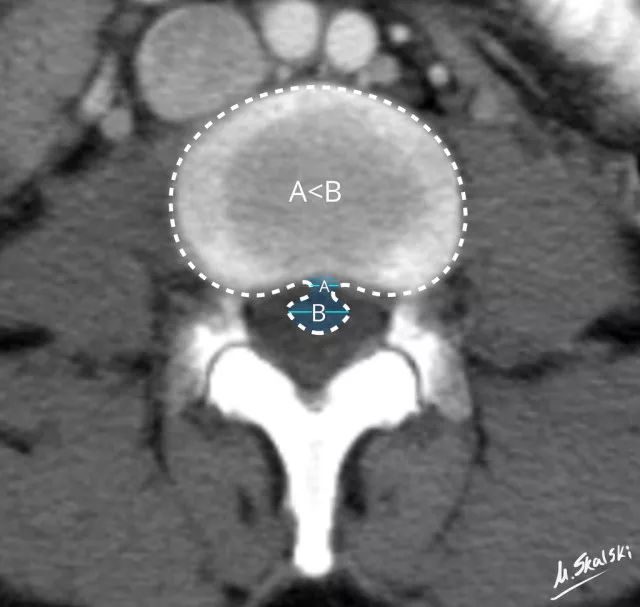

图 5 椎间盘突出的影像学定义为突出椎间盘的基底部(A)<突出组织的直径(B)